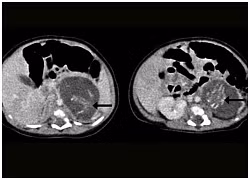

Vị trí xương sống của hai bào thai trong cơ thể bé nữ trong Bệnh viên Nữ hoàng Elizabeth tại Hong Kong. Ảnh: Tạp chí Medical.

Cặp bào thai song sinh có chân, tay, xương sống, xương sườn, dạ dày. Chúng có khối lượng lần lượt là 9,3 và 14,2 gram. Mỗi bào thai có một dây cuống rốn riêng.